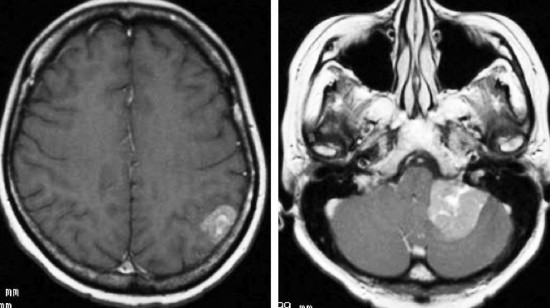

肺小細胞癌の転移 multiple metastases of lung small cell cancer

左のMRIは,肺小細胞癌の患者さんに脳転移が無いか確かめるために撮影されたものです。転移はありませんでした。右側のMRIは,そのわずか3週間後に撮影したものです。数十個の脳転移がありました。肺小細胞癌では短期間の間に無数の脳転移を生じることがあります。かつては脳転移を予防するための予防的全脳照射という治療が行われていたくらいです。